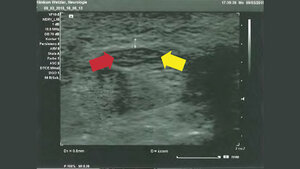

Premium Neurologie 01.03.16 Laura Isabel KochSonographie des Nervus medianus und des Nervus ulnarisNervensonographie Nervenultraschall hat sich in den letzten Jahren in der Neurologie zu einem vielgefragten und…